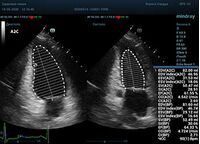

Что могут предложить современные приборы? Приборы нашего времени являются мощными вычислительными машинами, способными обрабатывать полученную информацию даже без помощи человека. Система автоматического вычисления фракции выброса – AUTO EF на приборах серии Resona компании Mindray сделает все за вас. За пару секунд прибор сам отыщет нужную фазу сердечного цикла и произведёт измерение и расчеты, а также покажет график изменения объема в сердечном цикле. От Вас требуется только получить качественное 4С и 2С сечение. Впрочем, прибор всегда оставляет возможность коррекции, если доктор имеет свое мнение на расположение точек планиметрии или момента измерения по ЭКГ каналу.